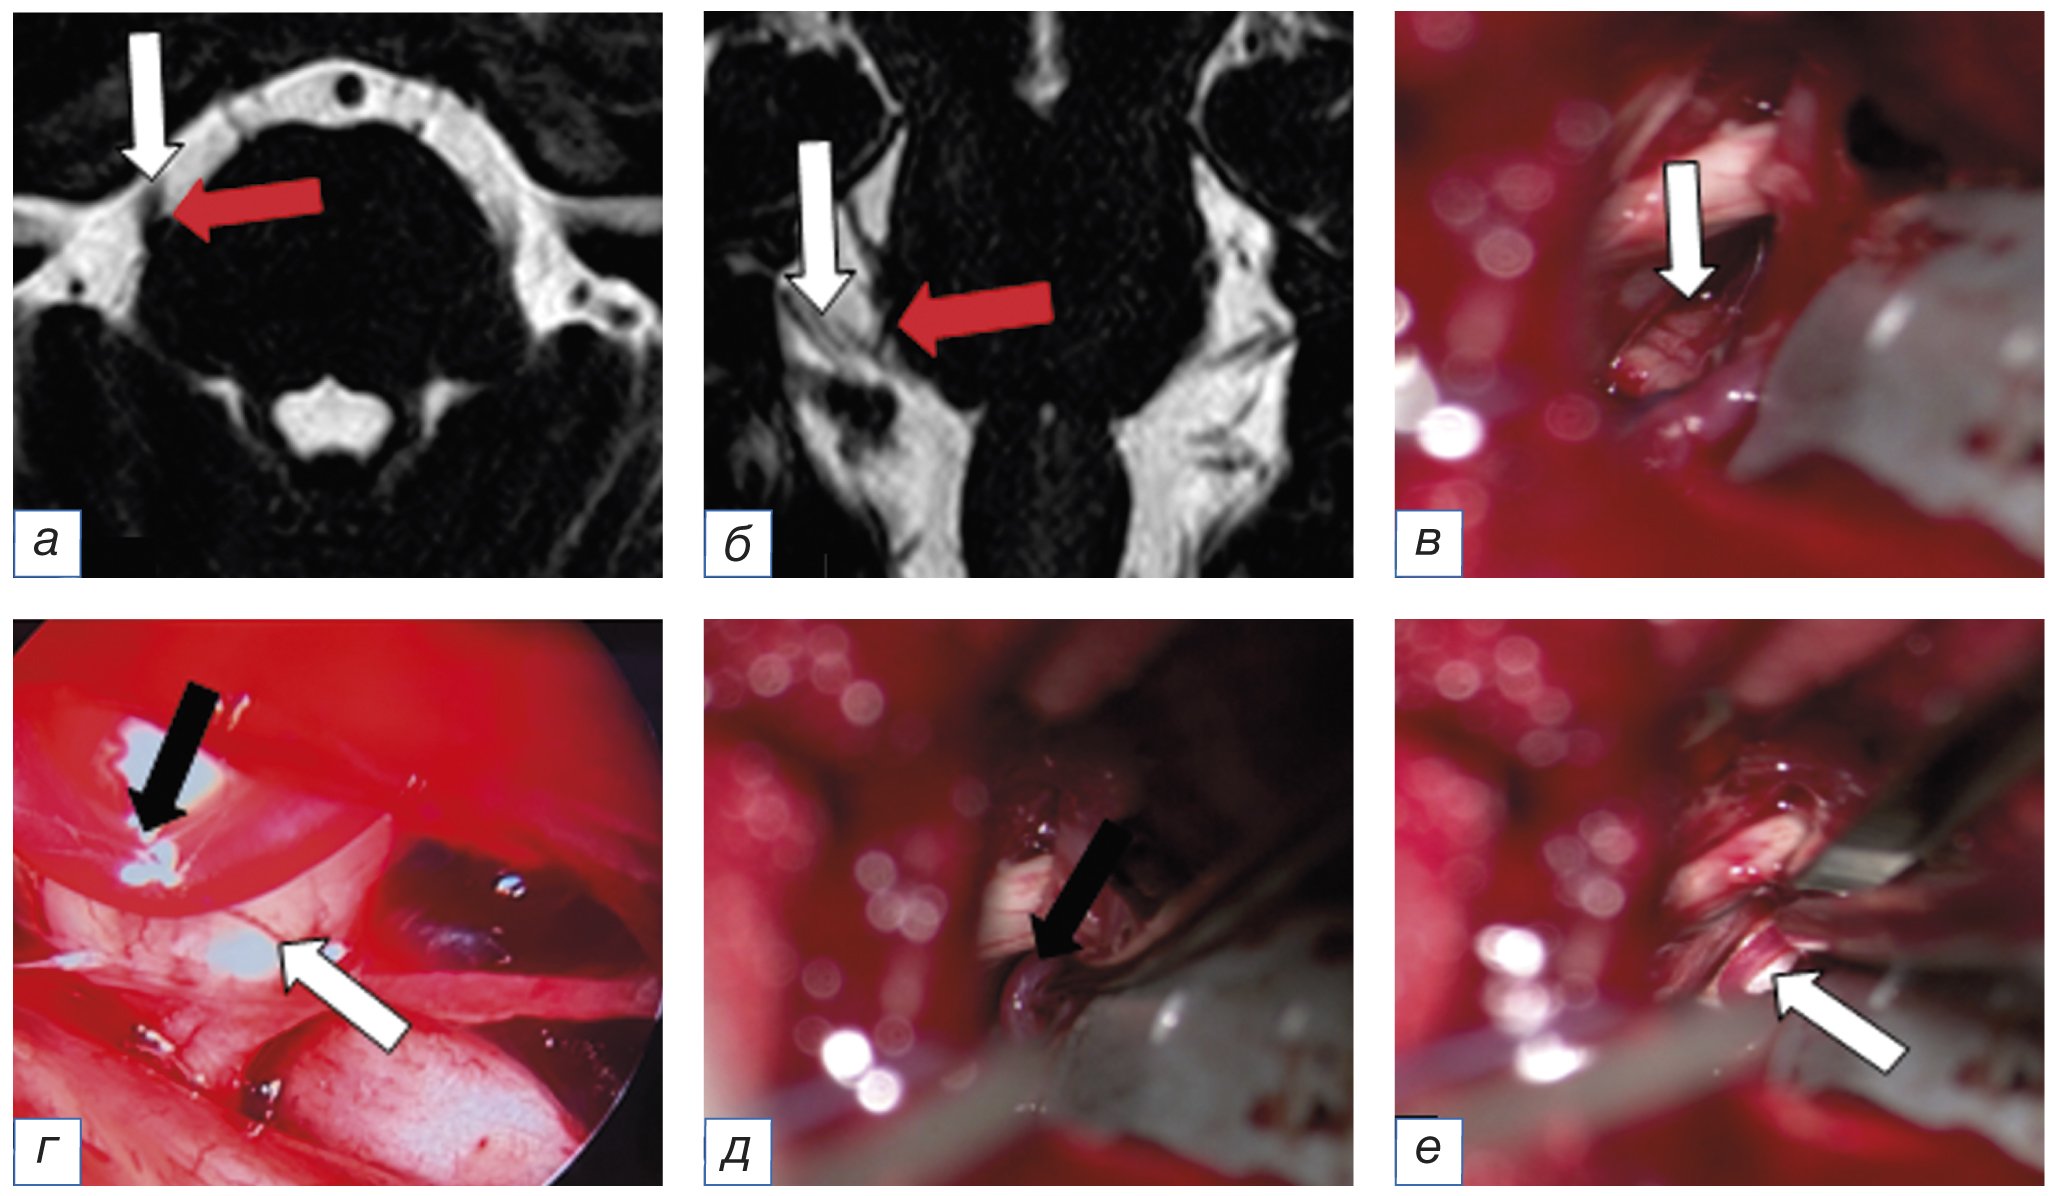

С целью визуализации компримирующих сосудов и контроля радикальности васкулярной декомпрессии у 12 (35%) пациентов кроме микроскопа дополнительно использовали видеоэндоскопию компании Karl Storz (Германия) диаметром 4 мм (угол обзора 0° и 70°) и Minop Invent компании Aesculap (Германия) диаметром 2,7 мм (угол обзора 30°); рис. 3.

Рис. 3. Пациент А. с невралгией тройничного нерва на фоне нейроваскулярного конфликта, выявленного при помощи интраоперационной видеоэндоскопии: а, б — магнитно-резонансная томография головного мозга в режиме FIESTA в аксиальной (а) и фронтальной плоскости, на которых выявлен нейроваскулярный конфликт между верхней мозжечковой артерией (красная стрелка) и корешком тройничного нерва (белая стрелка); в — интраоперационные снимки с микроскопа, на которых нейроваскулярный конфликт не выявлен (белая стрелка); г — интраоперационные снимки с эндоскопа Minop Invent (угол обзора 30°), на которых выявлена верхняя мозжечковая артерия (красная и черная стрелки) в проекции выхода корешка тройничного нерва из моста (белая стрелка); д — после микроваскулярной декомпрессии визуализирована верхняя мозжечковая артерия (стрелка); е — установлена тефлоновая прокладка (стрелка) между нервом и артерией. / Fig. 3. Patient A. with trigeminal neuralgia against the background of the neurovascular conflict, which was detected by intraoperative video endoscopy: а, б — magnetic resonance imaging of the brain in the FIESTA mode in the axial (а) and frontal planes, which revealed the neurovascular conflict between the superior cerebellar artery (red arrow) and the root of the trigeminal nerve (white arrow); в — intraoperative images from a microscope, in which the neurovascular conflict was not detected (arrow); г — intraoperative images from the Minop Invent endoscope (viewing angle 30°), which revealed the superior cerebellar artery (red and black arrow) in the projection of the exit of the trigeminal nerve root from the pons (white arrow); д — after microvascular decompression, the superior cerebellar artery was visualized (arrow); е — a Teflon gasket (arrow) was installed between the nerve and the artery.

Необходимость видеоэндоскопии во время микроваскулярной декомпрессии мы оценивали по трем критериям: I — улучшение визуализации зоны выхода корешка тройничного нерва из моста; II — эндоскопическое обнаружение нейроваскулярного конфликта, который не был виден через микроскоп; III — контроль радикальности микроваскулярной декомпрессии. Таким образом, у 7 (58%) из 12 пациентов с аНТН применение видеоэндоскопии во время микроваскулярной декомпрессии позволило улучшить визуализацию зоны выхода корешка тройничного нерва из моста (I критерий), у 2 (17%) больных обнаружили нейроваскулярный конфликт (II критерий), а у 3 (25%) провели контроль радикальности микроваскулярной декомпрессии.